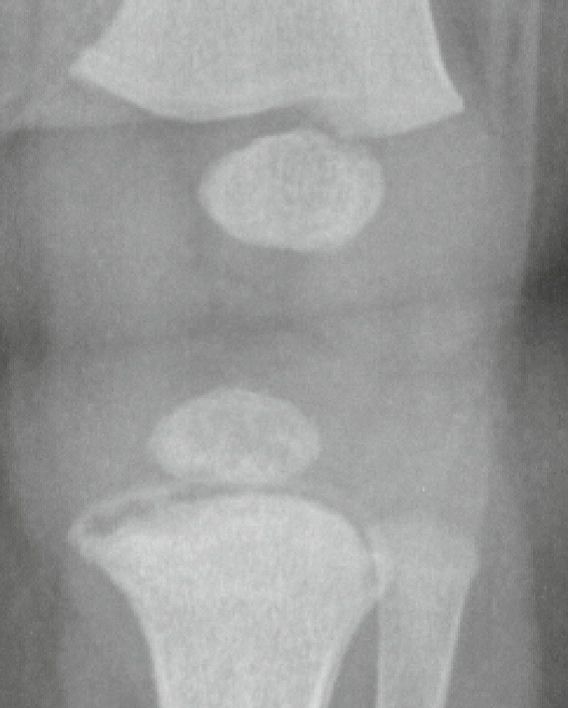

NAT - metaphyseal corner fracture

NAT - metaphyseal bucket handle fracture